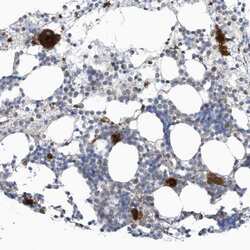

Supportive validation

- Submitted by

- Invitrogen Antibodies (provider)

- Main image

- Experimental details

- Immunohistochemical staining of GPATCH3 in human bone marrow using a GPATCH3 Polyclonal Antibody (Product # PA5-56918) shows cytoplasmic positivity in hematopoietic cells.